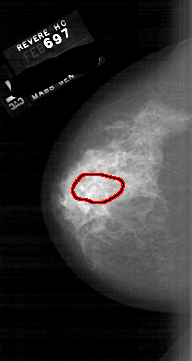

A_1667_1.LEFT_MLO

FILE: A_1667_1.LEFT_MLO.OVERLAY

TOTAL_ABNORMALITIES 1

ABNORMALITY 1

LESION_TYPE CALCIFICATION TYPE PLEOMORPHIC DISTRIBUTION SEGMENTAL

ASSESSMENT 4

SUBTLETY 3

PATHOLOGY MALIGNANT

TOTAL_OUTLINES 1

BOUNDARY